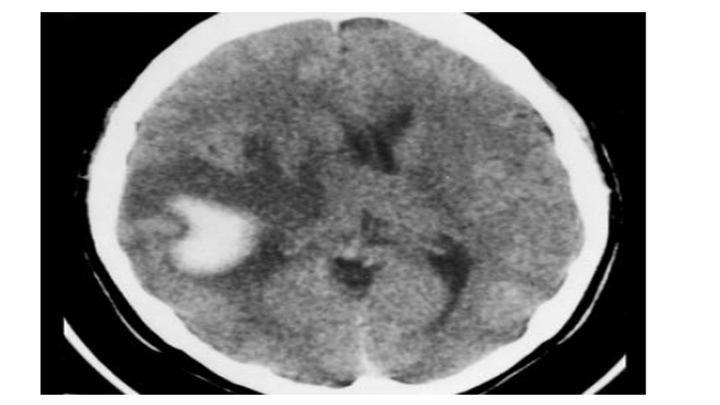

基底节区血肿,壳核消失(可与对侧比较观察),周围可见片状低密度区。在几天的时间里,血肿外围低密度区会逐渐增大。水肿部分因为血管的浆液性渗出从出血灶向外延伸至白质,部分是由于周围神经组织对血块的水肿反应。